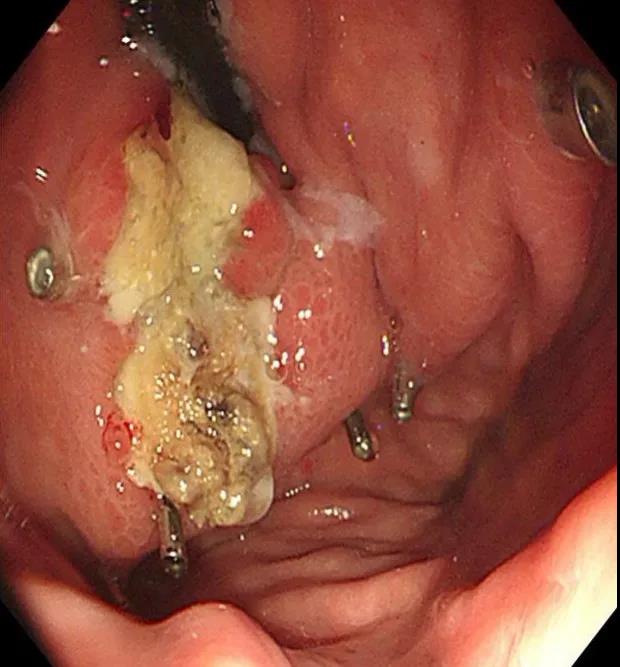

入院后予禁食、抑酸、補液、輸血處理,與家屬溝通,完善胃鏡檢查,結(jié)果示胃底巨大曲張靜脈團、門脈高壓性胃病。蓋偉主任考慮胃底靜脈團大、靜脈壓力高,合并分流道的可能性越大,且多數(shù)為胃脾分流,應首先完善門靜脈血管成像檢查,以明確血管情況。成像檢查結(jié)果符合食管胃底靜脈曲張CT表現(xiàn),胃底血管部分與脾靜脈相交通。

科室組織術前討論,共同讀片,分析:該患者巨大胃底靜脈曲張存在胃脾分流道,巨大者難以套扎,常規(guī)組織膠血管內(nèi)注射治療易引起異位栓塞。術前CT門脈成像檢查清晰顯示靜脈團的血管走行及血管的出入口大致在胃底的位置,鈦夾夾閉可以先行阻斷或減緩血流,隨后的組織膠治療不易發(fā)生異位栓塞。于是,團隊決定采用目前最新的鈦夾限流聯(lián)合組織膠栓塞術處理該患者的胃底曲張靜脈。

術前胃鏡及血管成像

術中治療:胃底鈦夾夾閉部分靜脈,分三處共注射組織膠3.5ml、聚桂醇6ml。